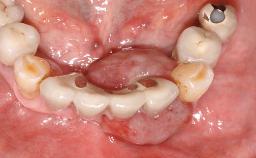

Removal of a Malpositioned Implant and Direct New Implant Placement with Simultaneous Contour Augmentation using GBR

A 35-year old female patient was referred to the Department of Oral Surgery and Stomatology at the University of Bern, Switzerland, for examination of an implant site that had exhibited clinical signs of slightly delayed wound healing. In addition, the referring clinician found no evidence for a facial bone wall when she raised a flap to gain access to the implant for abutment connection. Four months earlier, she had inserted a bone-level implant in a single-tooth gap, where the lateral incisor had been extracted due to a chronic periapical lesion on the mesial aspect of the root. Implant placement was combined with simultaneous bone augmentation using deproteinized bovine bone mineral (DBBM, Bio-Oss®; Geistlich, Wolhusen, Switzerland) and a collagen membrane (Bio- Gide®; Geistlich), followed by primary wound closure. The patient also provided the postsurgical radiograph that displayed the implant with a 3.5-mm healing cap.